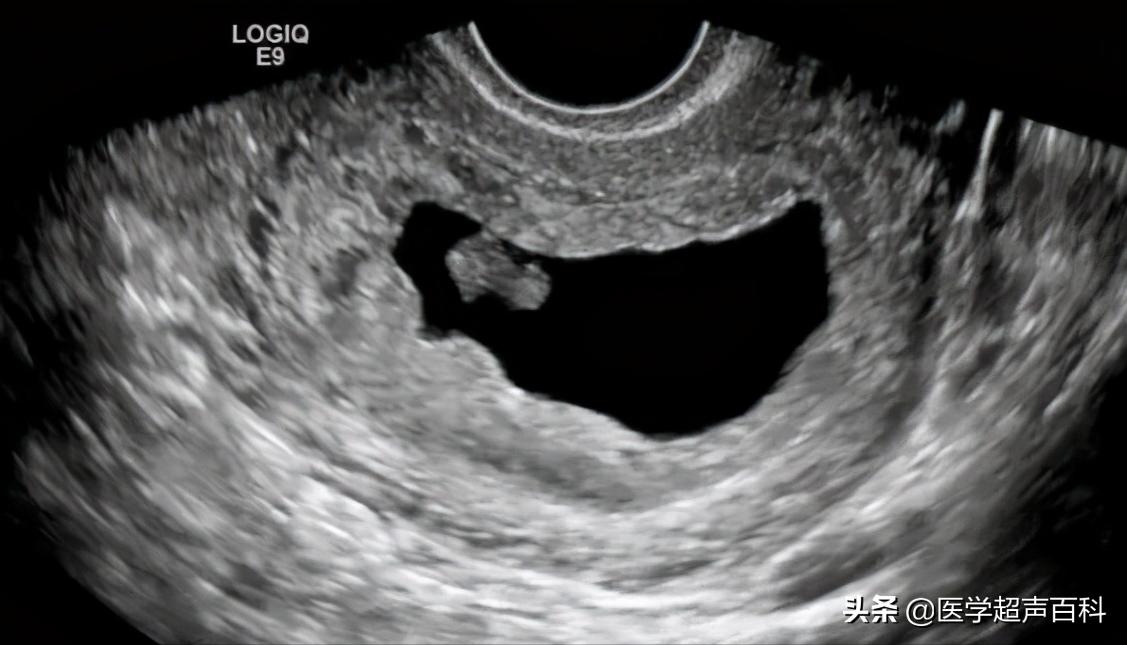

1、空孕囊是指受精卵着床后发育异常,尚未形成胚胎就停止发育。B超:宫腔内只有孕囊而无胚芽组织的异常妊娠。有时B超会描述只见液性暗区,内未见卵黄囊或胚芽。

2、有胚芽无胎心B超示妊娠囊内可见胚芽,但无胎心搏动。

3、有胎心后停育是指B超在动态监测妊娠囊,可以先有胎芽胎心搏动,待一段时间 B超又未监测到胎心搏动,只见枯萎的妊娠囊。

1、胚胎长度≤5mm,无心管搏动,7-10天后复查仍无心管搏动。

2、胚胎长度>5mm,无心管搏动或妊娠囊平均内径>20mm,无卵黄囊及胚胎。

3、妊娠囊平均内径≤20mm,无卵黄囊及胚胎,1-2周后复查仍无卵黄囊及胚胎。

可见胚胎停育是B超医生的描述术语,因为通过B超可以非常直观地看到正常胚胎的胎心搏动和胚胎停育中的无胎心搏动,因为通俗易懂,被患者及医生广泛接受。